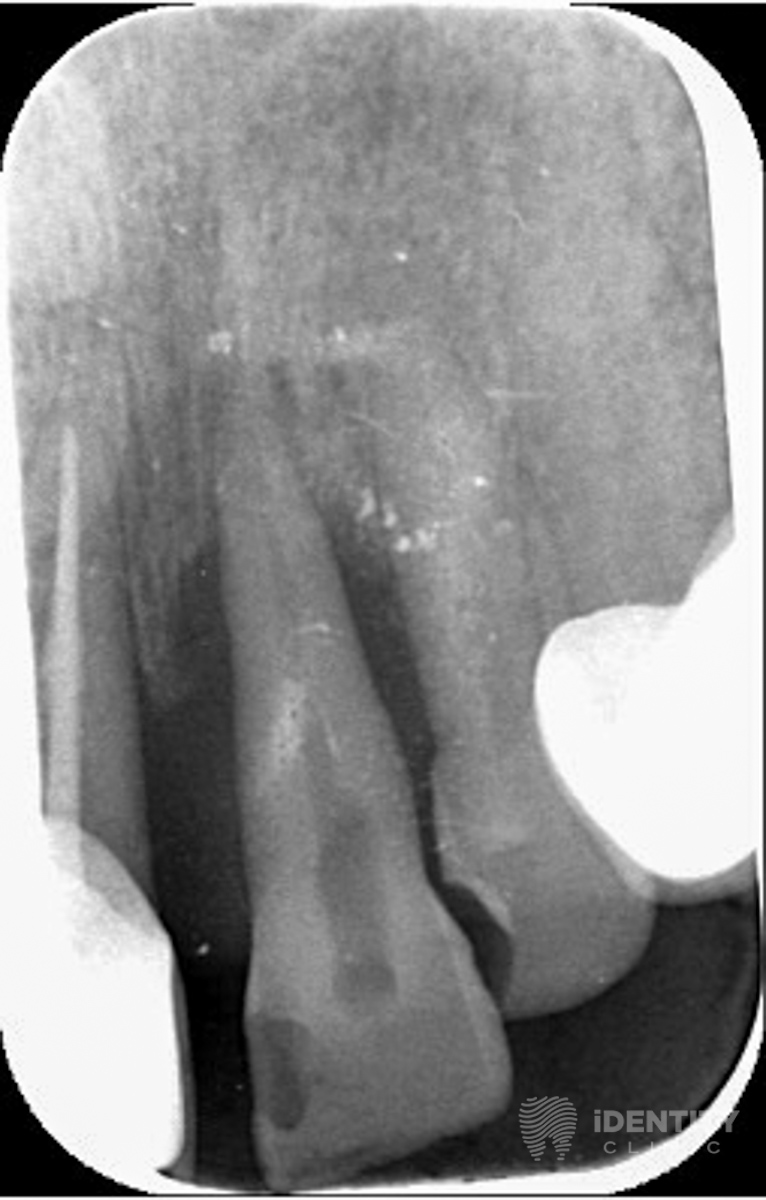

A páciens krónikus fogágybetegségben (közismertebb nevén fogínysorvadásban) szenved. A gyulladás következtében kisebb-nagyobb mértékben elpusztult a fogak tartószerkezetét jelentő csont a fogak körül.

A bal felső első fog körül már olyan nagy mértékű a csonthiány, hogy a fogat reménytelen prognózisa miatt eltávolításra ítéltük. A többi, szintén parodontalisan (fogágybetegség által) érintett fog teljeskörű parodontalis terápiájának megkezdése indokolt.